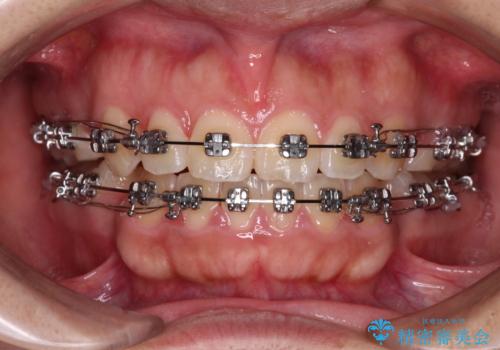

- メタルブラケット

上下の前歯が前方に突出していたため、上下左右の第一小臼歯4本を抜歯し、ワイヤー装置にて抜歯矯正を行うこととしました。

上下前歯部の被蓋関係を改善するの時間がかかり、3年間を要することとなりましたが、スッキリとした口元に仕上がりました。